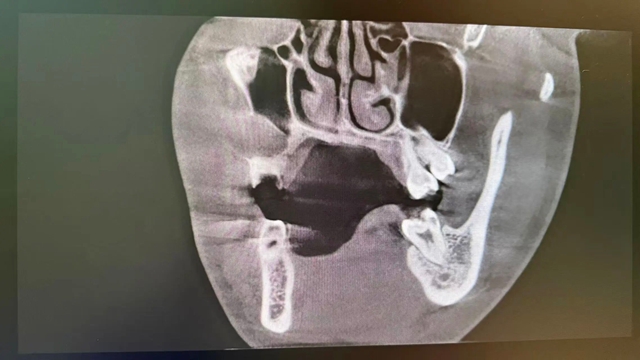

CBCT(三维口腔CT)影像检查显示:右上前磨牙残根的根尖位置,有一个直径约1.5cm×1.2cm的类圆形囊性阴影,边界清晰。囊肿与上颌窦腔之间仅隔着一层极薄的上颌窦壁,稍有不慎就可能导致口腔与上颌窦腔穿通,引发感染、口鼻漏等严重并发症。

术前“侦察”:依赖CBCT三维影像,医生能像拥有透视眼一样,看清囊肿的大小、范围、与重要结构(如上颌窦、神经)的距离,制定毫米级的手术方案。